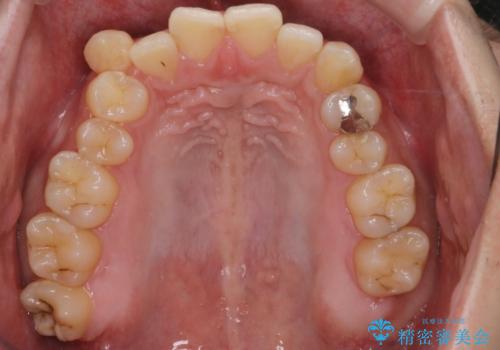

- 上の八重歯と下の歯のがたつきを主訴に来院されました。

矯正検査の結果、抜歯はせずに

臼歯を遠心移動させ、歯列をワイヤーで整えることでスペースを確保し、IPR(歯と歯の間を削る処置)を加えて歯並びを綺麗にする治療計画を立てました。

歯の移動にオープンコイルとMI(歯肉に埋入するネジ)を用いました。